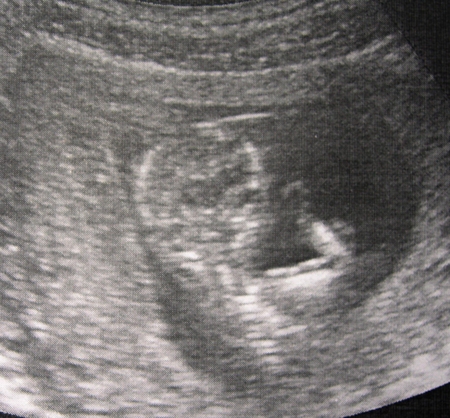

а тут мы улыбаемся))))))

))) как же это здорово, первое свидание запоминается навсегда)))